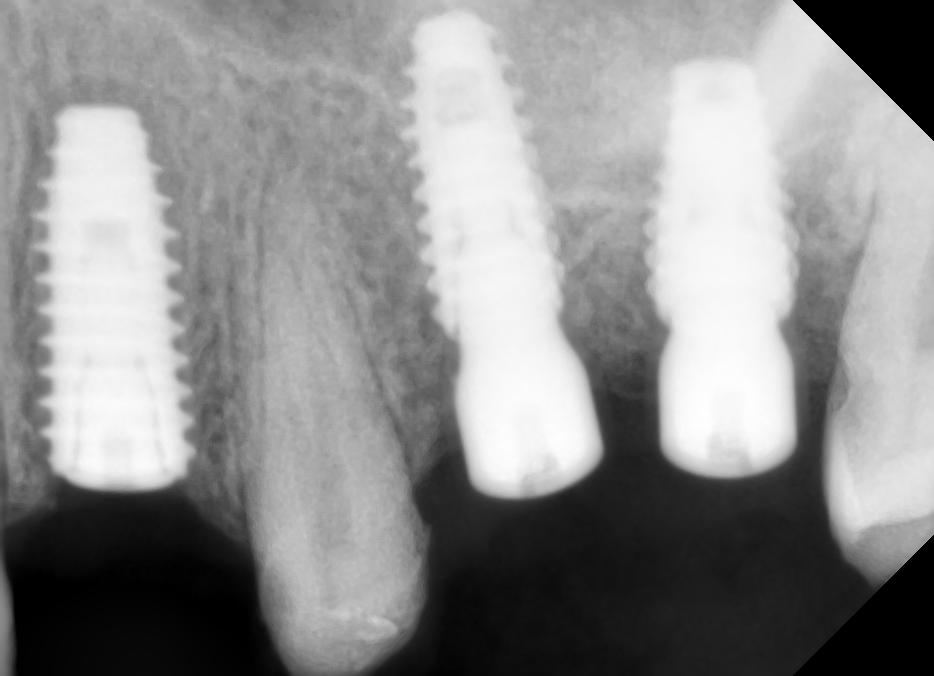

Cases